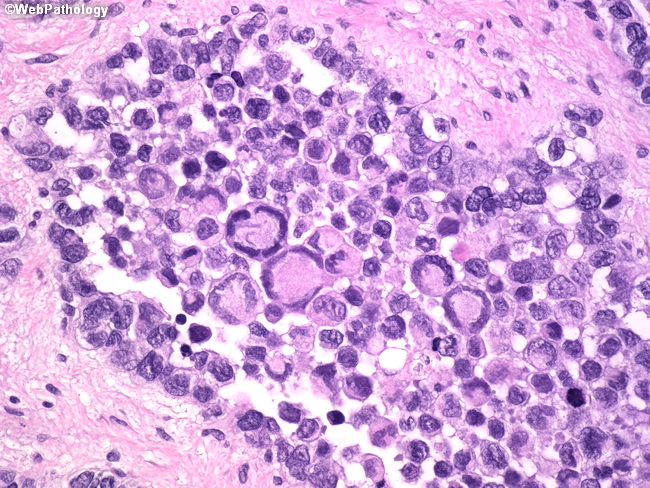

Webpathology.com: A Collection Of Surgical Pathology Images

www.webpathology.com

www.webpathology.com

rhabdomyosarcoma alveolar webpathology pathology comments microscopic

Rhabdomyosarcoma mri tissue sarcomas. Mesothelial cells ascites,mesothelial cells in ascitic fluid,reactive. Rhabdomyosarcoma alveolar webpathology pathology comments microscopic